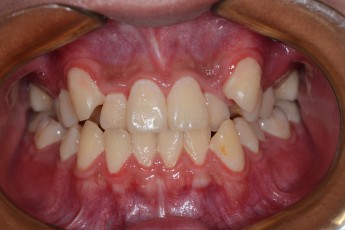

BEFORE & AFTER

- 덧니교정